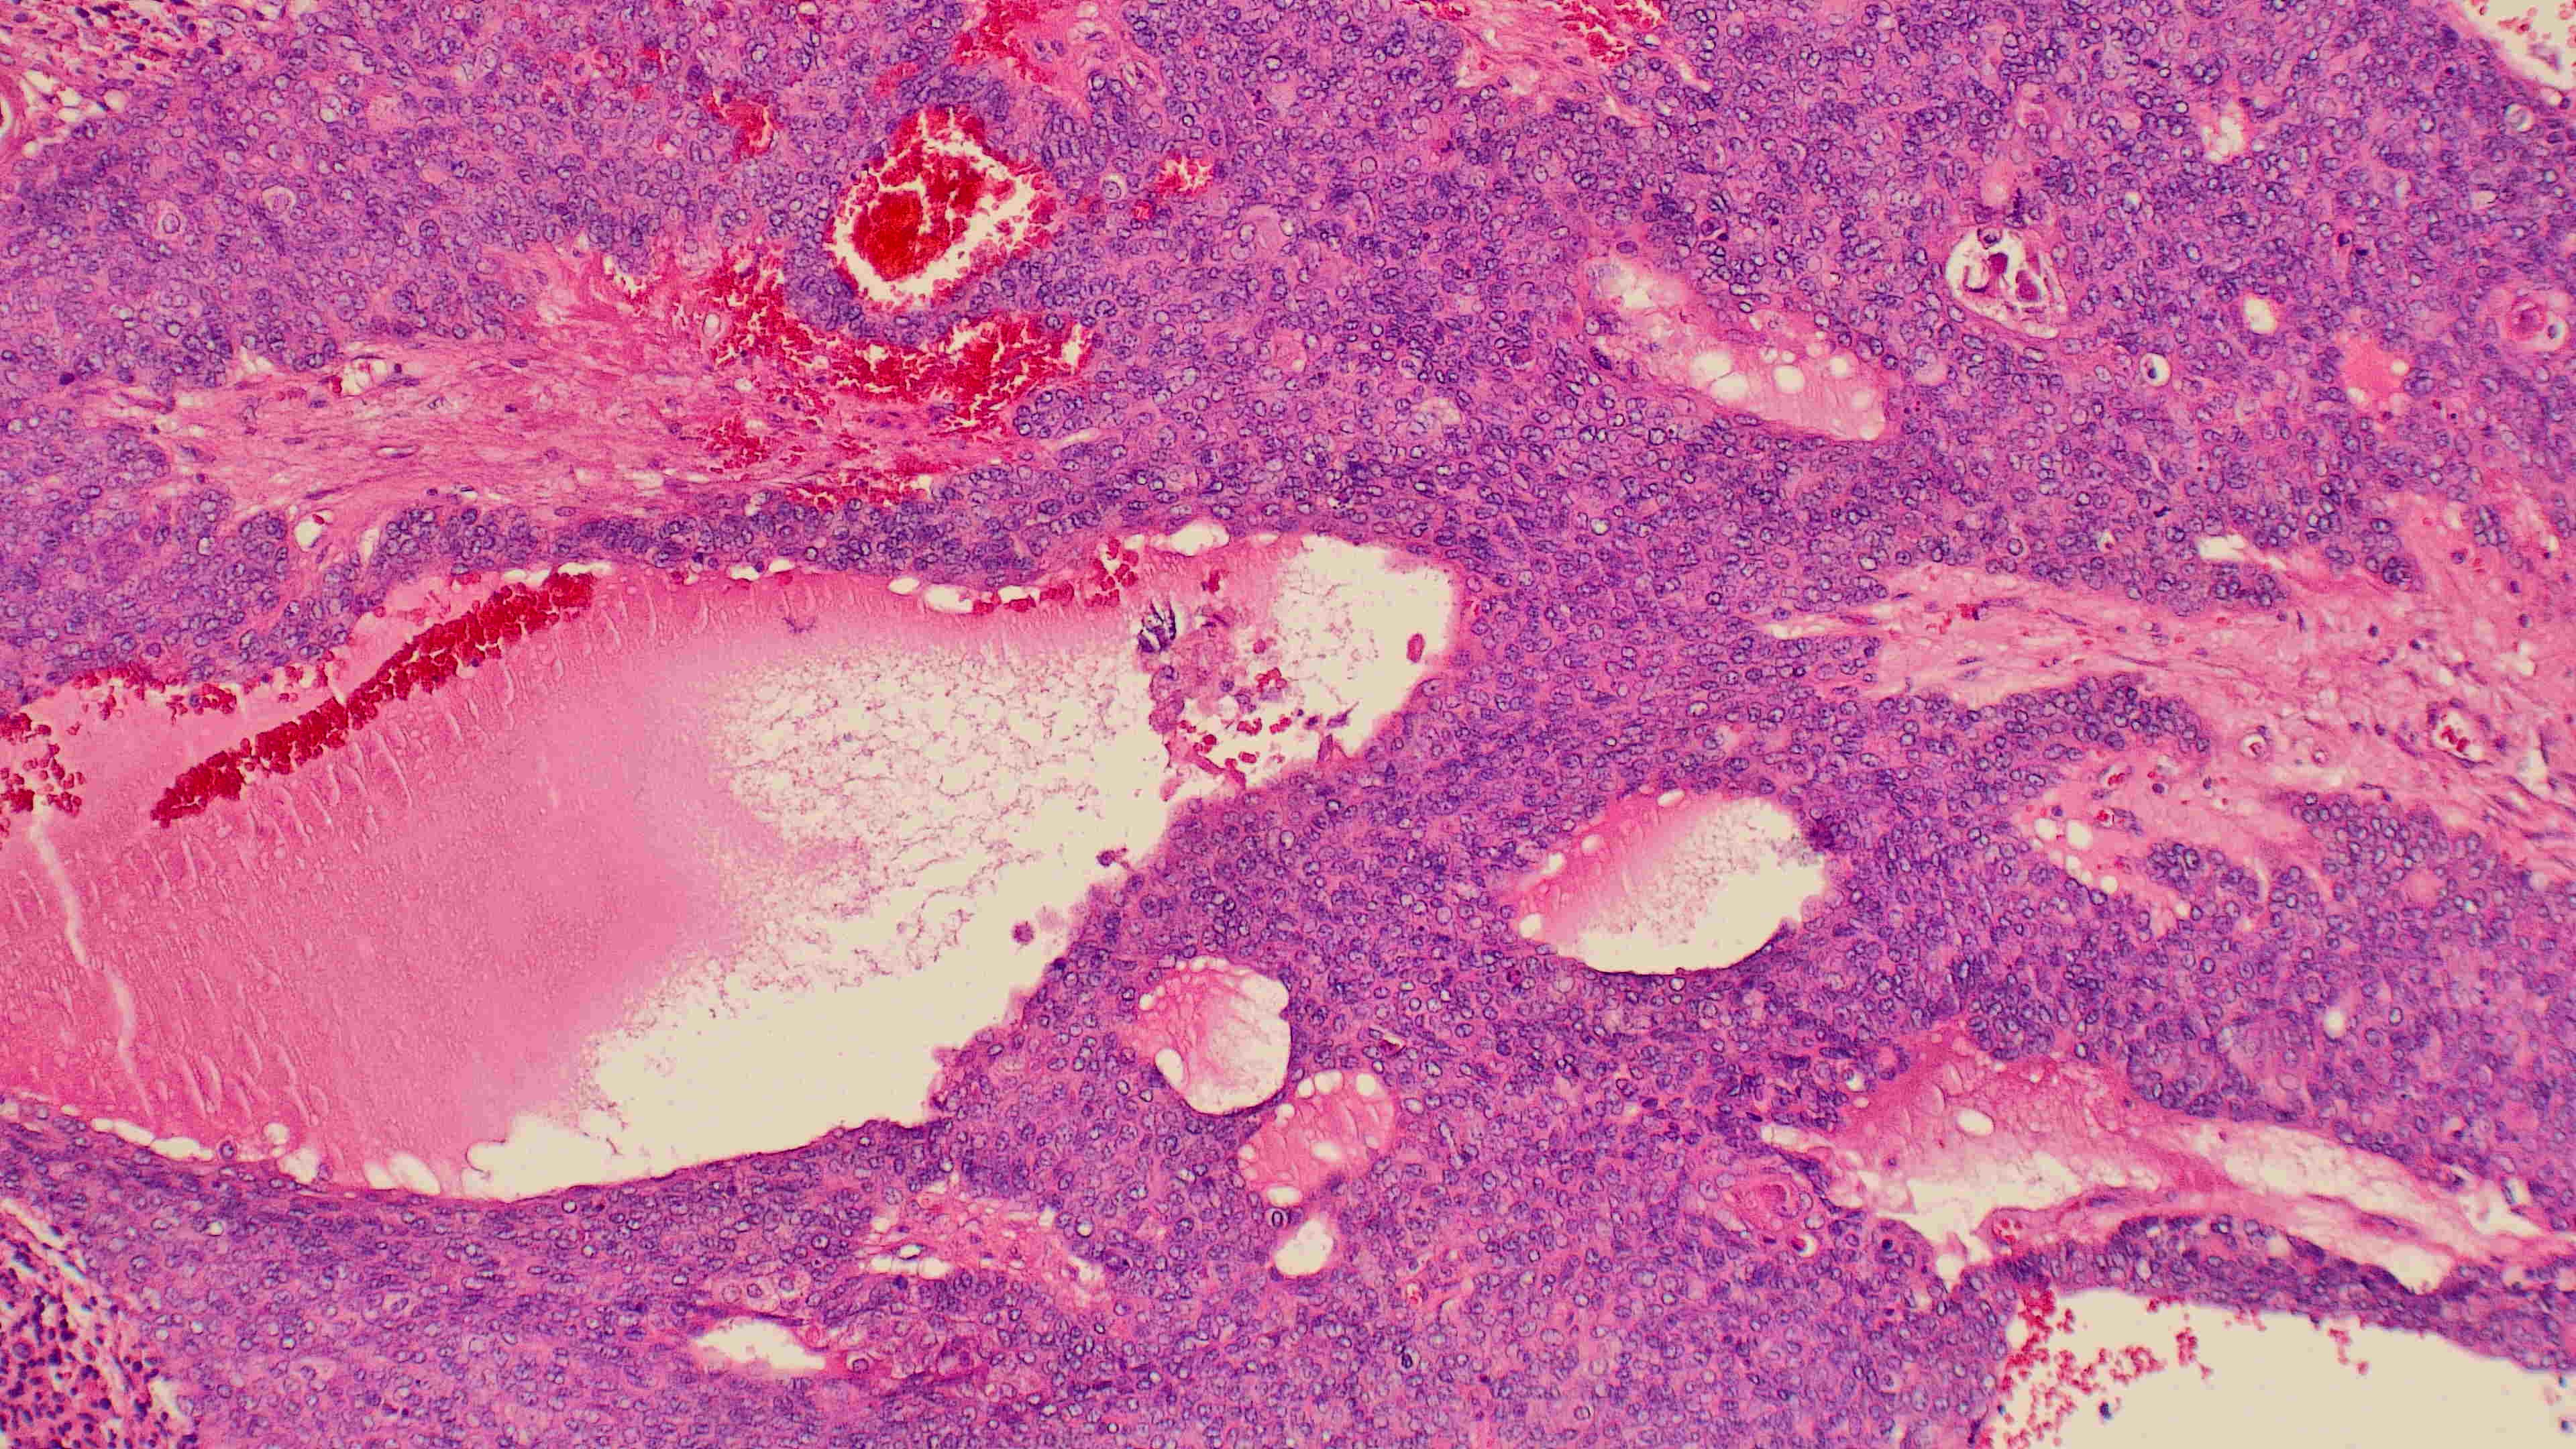

下巴肿物

带皮不规则组织3*3*2cm,切面灰白灰褐实性质软

会诊结果:小汗腺汗孔癌